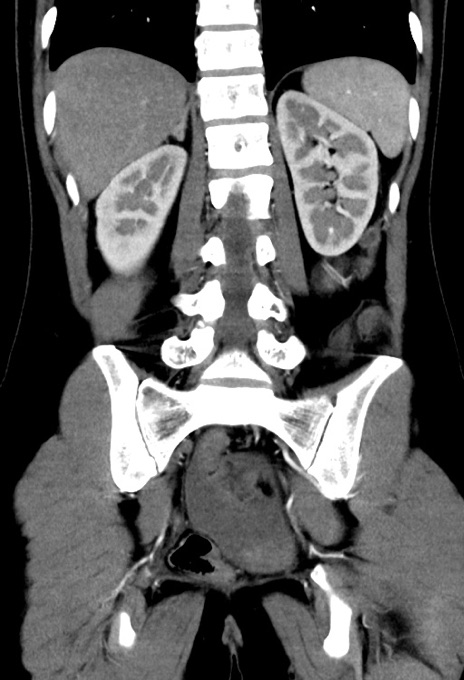

症例17(冠状断像)

【症例】20歳代女性

【主訴】嘔吐、下腹部痛

【現病歴】昨日夕食後に嘔吐し下腹部痛が出現。本日になっても嘔吐持続し改善しないため来院。

【身体所見】意識清明、BT 37.2℃、BP 108/67mmHg、腹部:平坦、やや硬、下腹部正中から右にかけて圧痛あり、反跳痛軽度あり、tapping pain(+)。

【データ】WBC 13600、CRP 14.94